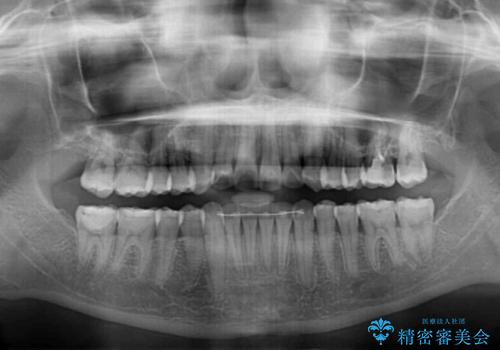

年に一度、夏休みの時期にしか帰国できないため、帰国のタイミングに合わせてマウスピース交換スケジュール治療計画としたため、3年半という期間を要しました。

留学先でもしっかりとマウスピースの装着を実践してくださったので、ご本人の満足のいく仕上がりとなりました。